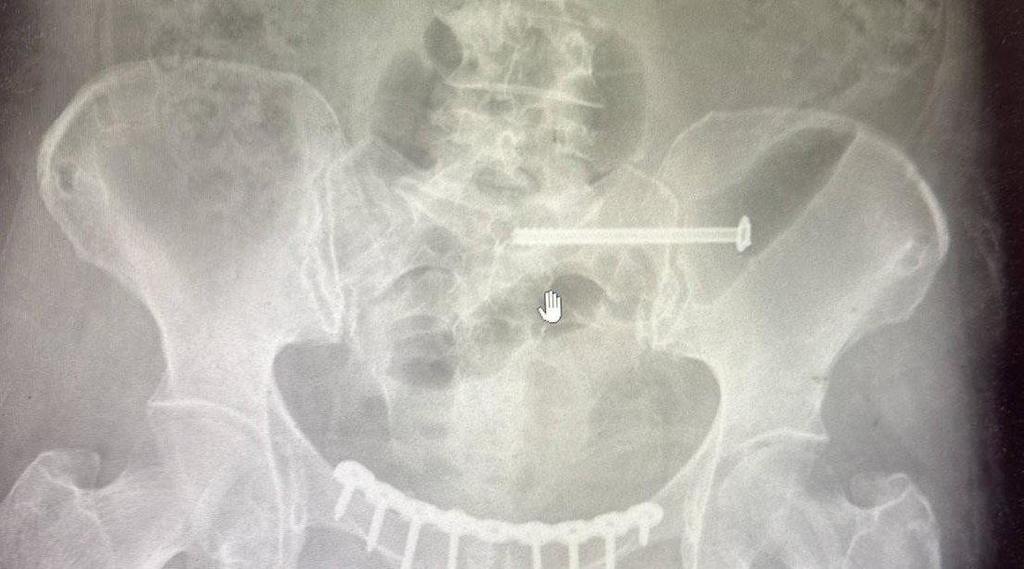

В ходе обследования врачи диагностировали сочетанную травму — разрыв лонного и крестцово-подвздошного сочленений, которые соединяют различные кости таза и играют важную роль в поддержании вертикального положения тела и распределении нагрузки. Было принято решение провести хирургическое лечение.

— Мы выполнили остеосинтез, то есть соединили обломки костей. Чтобы правильно их закрепить использовали специальные пластины и винты. В последующем их не потребуется удалять. И пластина, и винты из титана — биосовместимого материала, который не вызывает негативных реакций со стороны организма, и никак не помешает пациентке, — рассказал травматолог-ортопед Чеховской больницы Салман Асламханов.